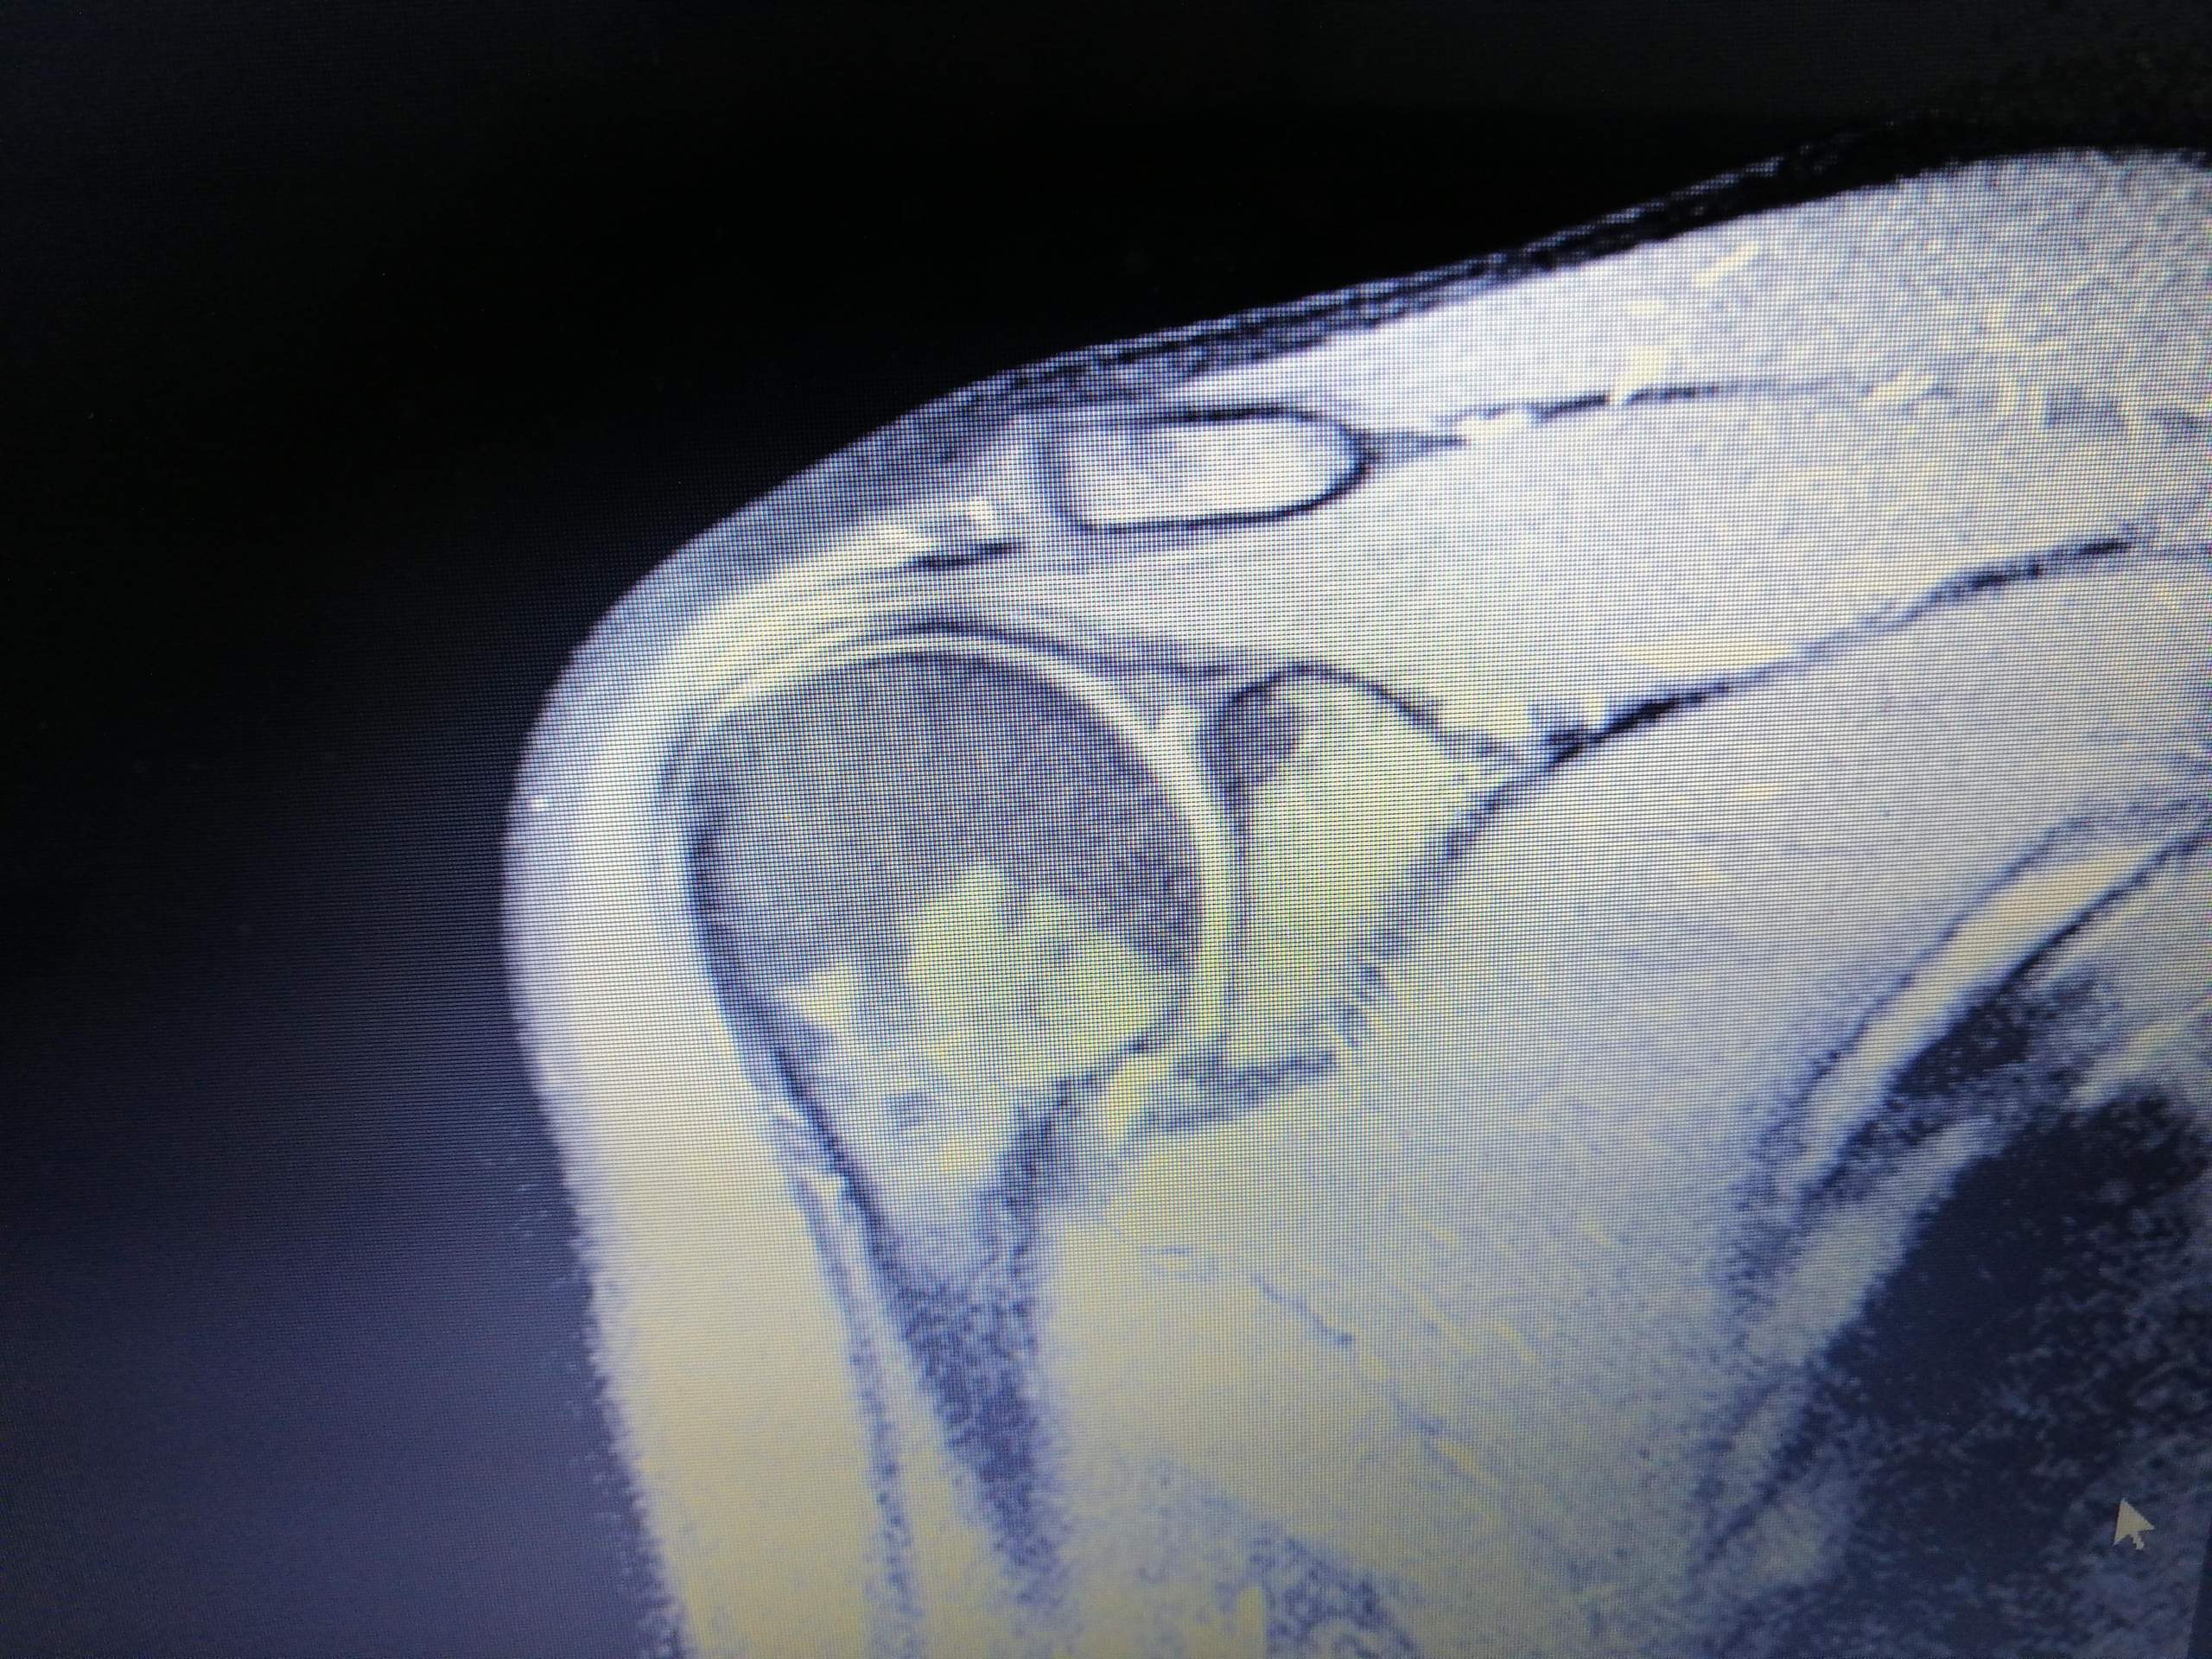

Besonders Weichteilgewebe (Organe, Gehirn, Nervengewebe, Muskeln etc. Ein MRT, beziehungsweise eine Kernspintomografie des Schulter- und Nackenbereichs ist oftmals die einzige . Die Sehnenentzündung wird auch Tendinitis genannt, oft wird umgangssprachlich aber auch die Sehnenscheidenentzündung gemeint, also eine .Einteilung nach Rockwood Bei dieser Einteilung werden 6 Typen der Verletzung unterschieden.Bereits kleine Schädigungen in der Schulter können für den Betroffenen starke Schmerzen verursachen.

Die Rotatorenmanschette besteht aus mehreren Muskeln, die . Trotzdem ist es entscheidend, eine optimale Therapie durchzuführen, um nach der gesamten Heilung wieder 100% Leistungsfähigkeit zu erreichen. Muskelfaserrisse zählen zu den besonders häufigen Sportverletzungen und sind bei Sportarten wie Fußball oder Handball typisch.Gut zu wissen: Eine Untersuchung des Ellenbogens wird in der Regel separat im Rahmen eines Ellenbogen-MRTs durchgeführt. Da das Schultergelenk zum Bewegungsapparat des Menschen gehört, der . Was sind die Symptome? Welche Behandlung hilft? Und .Die Schulter verbindet die obere Extremität mit dem Rumpf.Gut zu wissen: Eine Untersuchung des Ellenbogens wird in der Regel separat im Rahmen eines Ellenbogen-MRIs durchgeführt.Definition – Was ist ein MRT? Bei der Magnetresonanztomographie (MRT), auch Kernspintomographie genannt, handelt es sich um ein Diagnoseverfahren der .

Was sind die Symptome? Welche Behandlung hilft? Und wie lange dauert die .Definiton Eine Nervenwurzelentzündung, auch Radikulopathie, Radikulitis oder Wurzelneuritis genannt, beschreibt die Schädigung und Reizung einer Nervenwurzel an der Wirbelsäule.Zudem ist eine normale Beweglichkeit des betroffenen Arms in der Regel nicht mehr möglich. Er kann sehr schmerzhaft sein und erfordert viel Geduld.Wie funktioniert eine MRT der Schulter? Der Kernspintomograph besteht aus einer Vielzahl von starken Elektromagneten, die um den Patienten angeordnet sind. Das Material der Bandscheibe kann bei einem Bandscheibenvorfall in verschiedene Richtungen austreten, meist jedoch so, dass direkter Druck auf die Nervenwurzel entsteht. Bei Typ 1 liegt eine Dehnung des acromioclavicularen Bandes vor und der Patient verspürt einen geringen Druck- und Bewegungsschmerz. Häufig werden spezielle .Meistens handelt es sich um stechende und brennende Schmerzen und der Betroffene hat sofort das Gefühl, dass etwas mit dem Arm nicht stimmt und dies lässt ihn in eine Schonhaltung gehen.Die Magnetresonanztomographie (kurz: MRT) ist ein Verfahren der bildgebenden Diagnostik.Symptome eines Kapselrisses Ein Kapselriss ist sehr schmerzhaft, weil die Gelenkkapsel mit sehr vielen Schmerzrezeptoren ausgestattet ist.Da beim Einreißen der Kapsel auch .

MRT des Schultergelenks